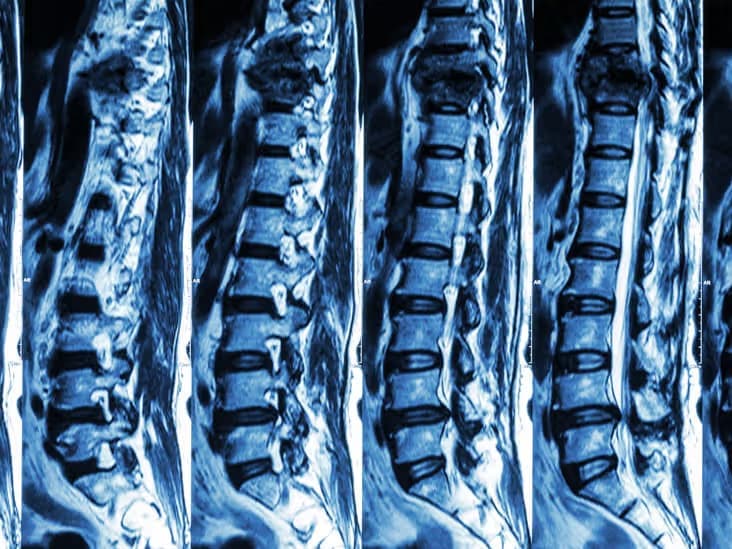

Комп'ютерна томографія хребта — це високоточний метод діагностики, який дозволяє детально візуалізувати структури хребетного стовпа, включаючи хребці, міжхребцеві диски, спинний мозок та навколишні м'які тканини.

КТ хребта забезпечує найкращу візуалізацію кісткових структур і є незамінним методом для діагностики переломів, деформацій, пухлин та дегенеративних змін хребта.

КТ краще показує кісткові структури, переломи, кальцифікати та підходить для пацієнтів з металевими імплантатами. МРТ краще візуалізує м'які тканини, спинний мозок, диски та корінці нервів. Вибір методу залежить від клінічної ситуації та має визначатися лікарем.